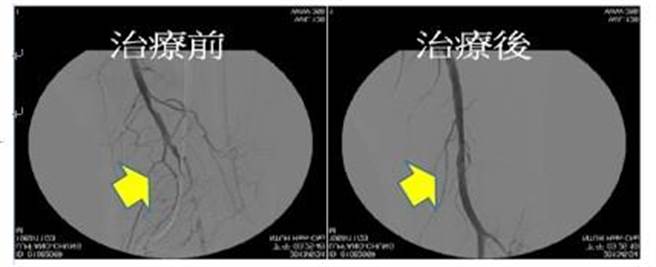

70岁的蔡阿嬷患有高血压和糖尿病,定期在诊所洗肾治疗,因四肢冰冷、心臟不舒服由诊所医师转诊至台大医院新竹分院进行血管摄影检查,发现心臟冠状动脉与脚部血管都有严重阻塞情形。心臟血管内科医师潘恒宇表示,周边血管阻塞是一种渐进式的慢性疾病,洗肾与糖尿病人是高危险群。

周边血管阻塞初期几乎毫无症状,后来因为足趾伤口久难癒合与四肢末梢疼痛,最后进展到足趾变黑坏死,才被发现是血管阻塞导致。潘恒宇表示,洗肾与糖尿病人是高危险群,另外患有三高、抽菸、肥胖、家族史的中老年人,也需特别注意。

台大医院新竹分院心臟血管科是新竹地区第一个进行的下肢动脉气球扩张术的医院,也是竹苗地区执行下肢周边血管导管治疗案例数最多的医院,心臟内外科合计1年共治疗300例以上,治疗所引起的併发症低于0.5%。